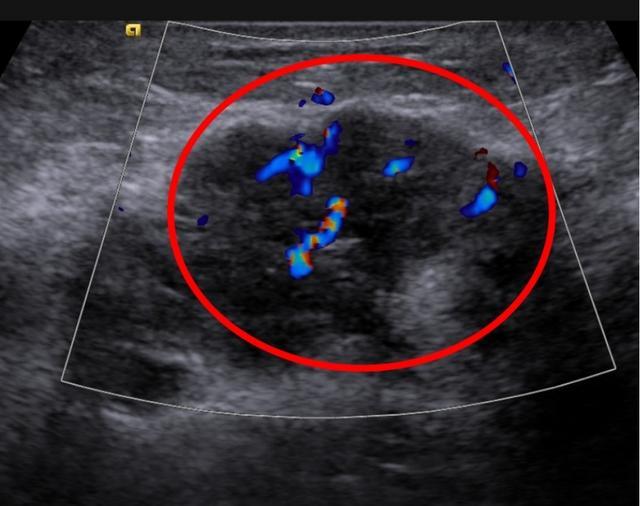

▲彩色多普勒显示结节内血流丰富杂乱

乳腺内形态不规则的低回声结节或肿块,边界不清,周边可见毛刺或强回声晕,后方回声衰减,可出现微钙化,彩色多普勒显示,肿块内血流信号增多,血流形态不规则,有高速高阻性频谱(阻力指数大于0.7)。